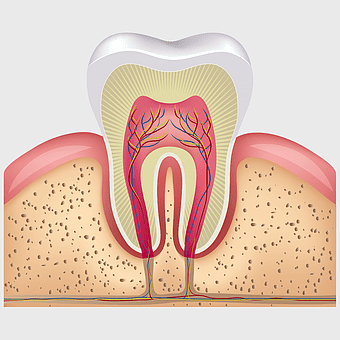

Tooth decay illustration, dental anatomy under magnification, pediatric dentistry cavity, dental public health awareness, tooth cross-section analysis, dental health education visuals, oral hygiene inspection tools, PNG

- tooth decay illustration

- dental anatomy under magnification

- tooth cross-section analysis

- dental health education visuals

Human tooth pulp anatomy, root canal therapy process, tooth decay illustration, teeth cross section detail, dental health guide, oral anatomy visuals, endodontic treatment steps -